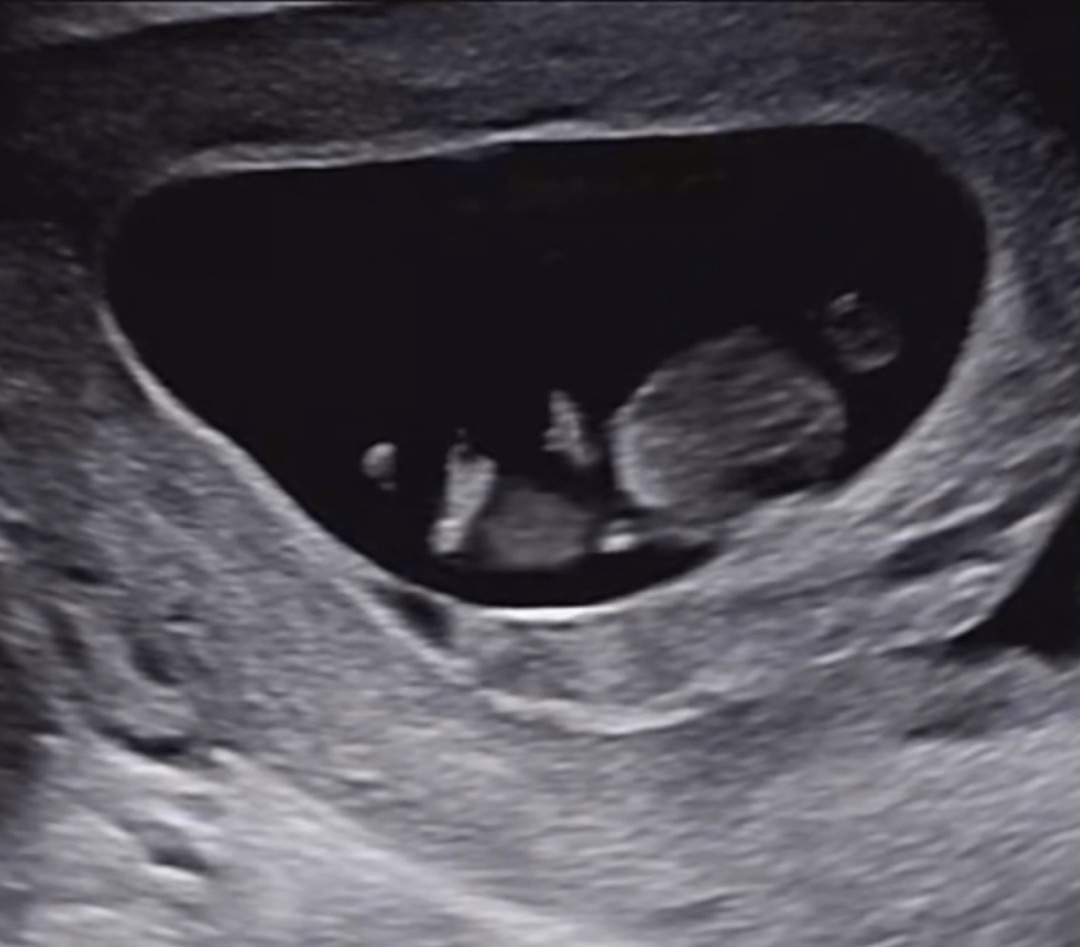

10주차 꼬물이

엄청 활발하게 뛰어다녀서 감동했어용!!